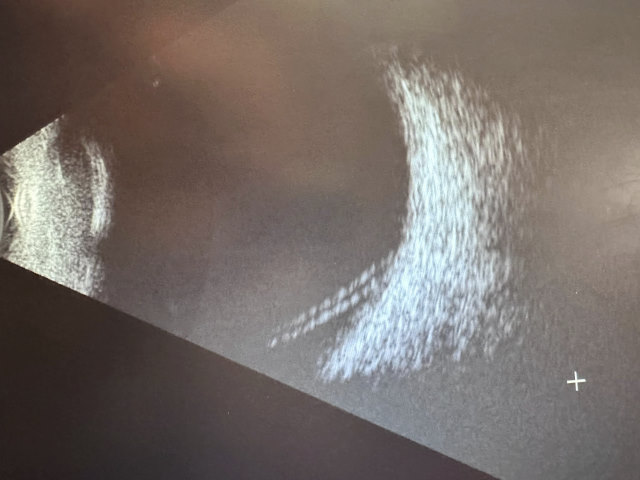

I know two people who had partial detachments and were not able to able to treat them as quickly as they should have. One has regained full vision, the other never will. Fortunately, I noticed the symptoms, went to specialists three times, and during the third visit, Doctor Eugene Ng (to whom I’m most grateful) said “uh-oh”. This is not something you want to hear. We did the ultrasound and saw it was clearly torn. The two lines at the bottom of this ultrasound image are my retina pulling off the back of my eye. I went for emergency surgery later that day. That entailed flying from the Big Island of Hawaii to Oahu which is about a 30 minute flight away, where they have a hospital with appropriate specialized equipment and trained nurses to support the surgeon. We came back the next day and I then spent the following week working from my phone lying face down and/or lying on my side looking at the palm trees and listening to podcasts. Thankfully I had Janet and other family members around to help out. And then 4 weeks later, going in for a routine post-op checkup, we found some anomalies, went to a specialist who did the deep imaging, and found that I have yet another partial detachment in evidence. Hence surgery #2 which is a little different and hopefully will be a once-and-for-all fix. Dr. Eng used a series of laser zaps. Imagine looking into a bright light and the doc looking through a special lens to see the places to fix and he pulls the trigger and a laser cooks a little bit of your eye to make the scar tissue hold it all together. I’ve done this twice now, which hopefully is all that’s needed. I will not know that for another month or two, but everyone is fairly confident that this will work.